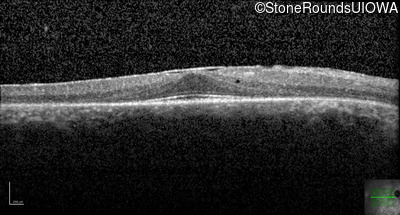

Optical Coherence Tomography - Left - 20/20

Exemplar / OCT Stack

OCT Stack